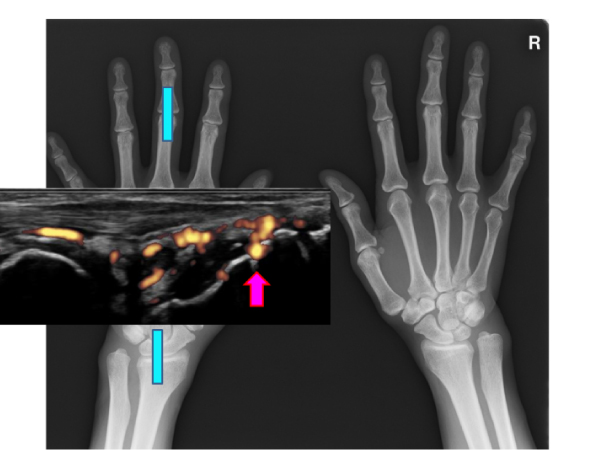

手の X 線写真は、骨や軟組織などの手の内部構造を示す白黒画像です。この診断ツールは、医師が片手または両手に影響を与える怪我や変性疾患を特定し、理解するのに役立ちます。医師は手の X 線を使用して手の骨の成長を監視することもできます。栄養不足や代謝障害がある場合、骨が適切に成長しない可能性があります。

レントゲン検査の結果がすぐにわかる場合もあります。たとえば、手首の骨折などの怪我は、迅速に診断して治療する必要があります。最新の X 線装置の多くは、写真が撮影されるとすぐにコンピューター画面に画像を表示します。骨や宝石などの密度の高い物体は、X 線フィルム上では白く写ります。軟部組織は灰色に見えます。関節の間などの空気は黒く見えます。